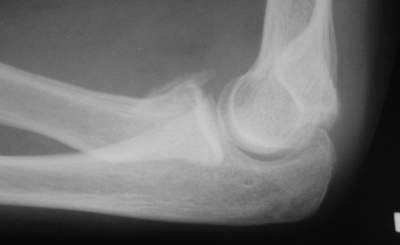

Есть методика воздействия на дистальный отломок при фиксации головки на месте - у нас - по-Марксу, у "них" - по-Паттерсону (ежели не обшибся с фамилией)...Есть методика прямого воздействия на проксимальный фрагмент... Путем пальцевого давоения... Вроде бы по-Ворохобову... у нас... Также делают и у "них"...Есть и как бы "промежуточная" методика в виде "давления" в сочетании с "накатом" - описана в каком-то вольюме JBJS, вроде бы израильскими (?)авторами...А есть еще метод по-Свинухову...Аналога у "них" мне не известно...О чрескожных манипуляциях спицами сознательно не упомянаю...Что предпочитаете?-------------------------А вот case report...Подросток 14 лет...Зкрытая репозиция "давление-накатом"... Безрезультатно...Через 3 дня репозиция по-Свинухову...Вроде бы все закончилось успешно...Однако 6 мес спустя после 2-кратного курса реабилитации клническая картина достаточно плачевна:Ротация предплечья:справа (здоровая) - 80 кнутри и 85-90 кнаружислева (больная) - 40 кнутри и 40 кнаружи При этом клинически внутренняя ротация справа (здоровая сторона) и слева (больная сторона) составляет порядка 85 и 80-75 соответвенно, но за счет ротационной мобильности запястья, порядка, например, 40-35 градусов на больной стороне...Сгибание слева (травмированная сторона) - 90 гр.разгибание - около 160 гр.Рентгенологически:в боковой проекции гетеротопическая оссификация по передней поверхности локтевого сустава, над головкой луча с "шипом" над радиокапителлярным сочленением...однако в прямой проекции локализация оссификата трудно определима, хотя вроде бы располагается по ходу сухожилия бицепса, т.е. в проекции луче-локтевого сочленения, но со стороны локтевой кости....Что делать?Кто виноват?:-)